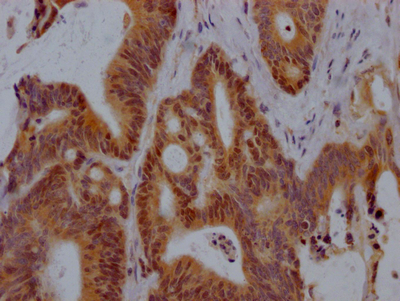

Immunohistochemistry of paraffin-embedded human glioma using CSB-PA018733LA01HU at dilution of 1:100